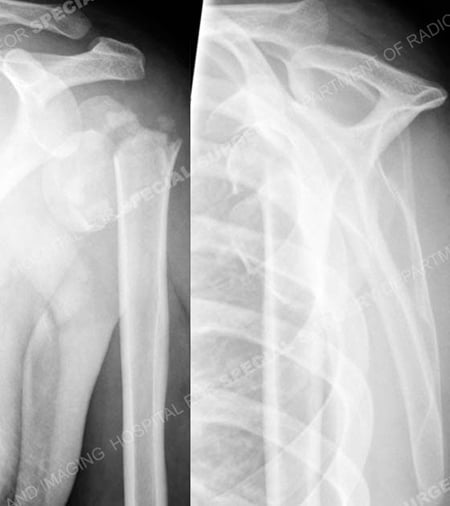

Radiographs of proximal humerus fracture and associated shoulder dislocation from a case example presented by the orthopedic trauma service at Hospital for Special Surgery.

Anteroposterior and lateral radiographs a comminuted 4-part proximal humerus fracture and associated shoulder dislocation with medial comminution.